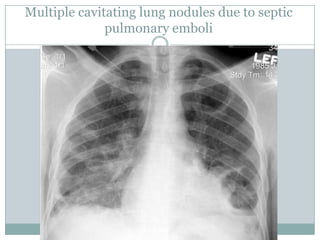

Chest radiograph

--Evidence of septic pulmonary emboli. In such cases,

there may be a few or multiple focal lung infiltrates,

which may reveal central cavitation.

--Rarely, chest radiographs show calcification in a

cardiac valve, which may raise suspicions of

endocarditis in a febrile patient.

Multiple cavitating lung nodules due to septic

pulmonary emboli